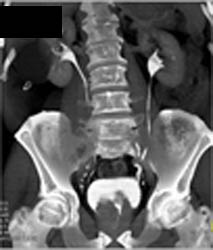

Diagnosis

Dilated Aortic Sinus